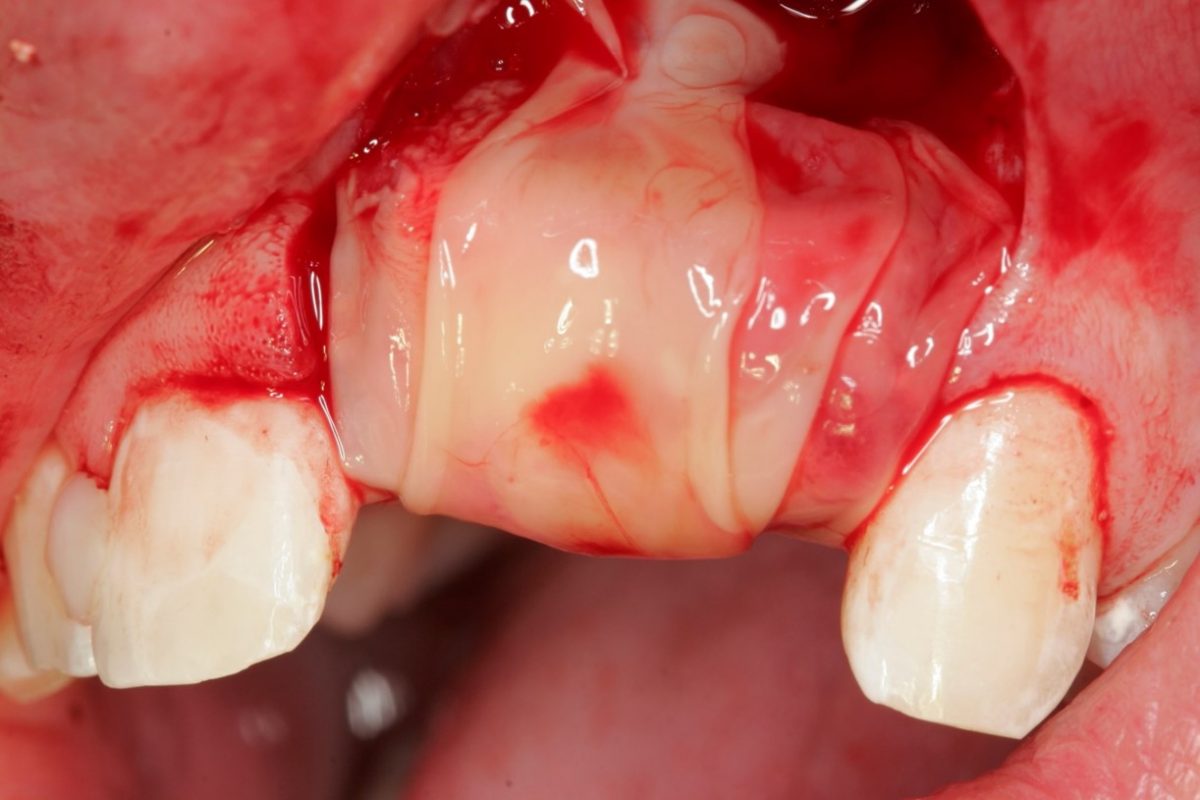

- Sinus lift

- Augmentace extrakčního lůžka

- Augmentace kostních defektů